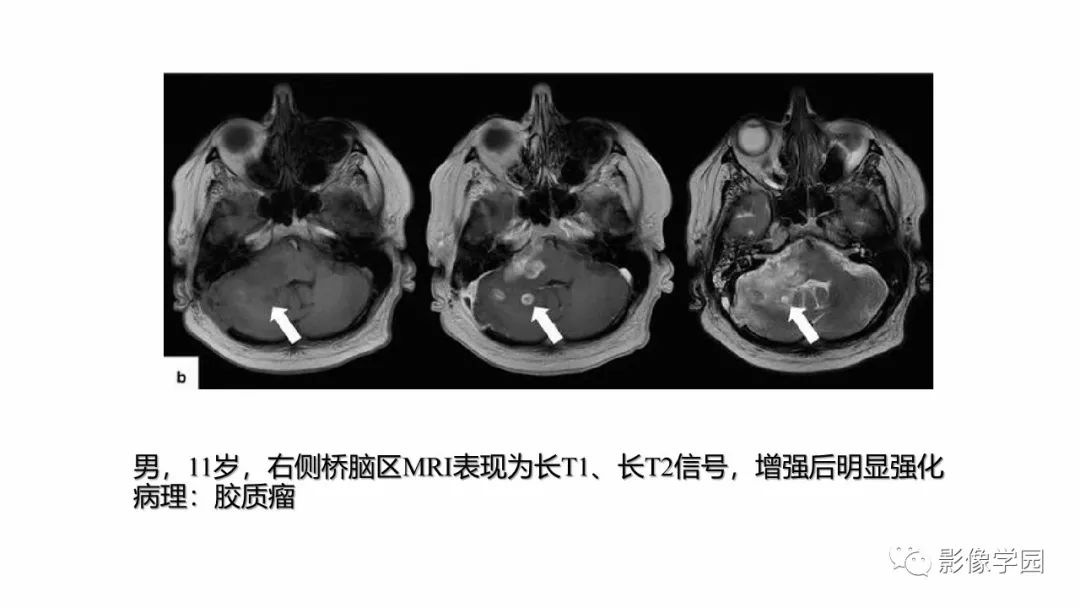

脑干病变的影像学表现